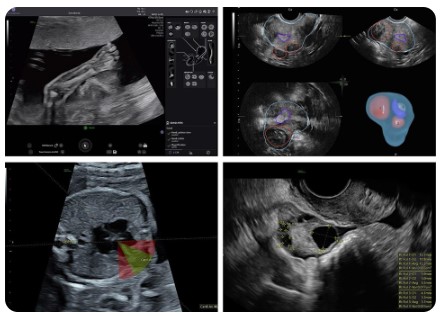

GE Healthcare VOLUSON Performance 18

Voluson Performance 18

Voluson Performance 18 – prosty, intuicyjny, spersonalizowany

Voluson Performance 18 został zaprojektowany, by być przyjaznym towarzyszem codzienności lekarza – kompaktowy, prosty w obsłudze i intuicyjnie dostosowujący się do potrzeb. Ten system ultrasonograficzny łączy wysoką jakość obrazu, zaawansowane narzędzia AI oraz ergonomiczny design, oferując kompleksowe wsparcie w diagnostyce.

Obrazowanie – szybko i precyzyjnie

• Doskonała jakość obrazu z automatyczną optymalizacją – szybkie i pewne skany, nawet przy różnych typach pacjentek.

• Radiantflow™ – zaawansowany kolorowy Doppler 3D-like, uwidaczniający nawet najmniejsze naczynia krwionośne.

• Flow Profiles – predefiniowane ustawienia kolorowego i spektralnego Dopplera, skracające czas badania nawet o 56 %.

• Shadow Reduction – redukcja cieni na obrazach B-mode, przywracająca widoczność tkanek i granic struktur.

Sztuczna inteligencja i automatyzacja

• SonoLyst – automatyczne wykrywanie i oznaczanie anatomii płodu, redukujące liczbę naciśnięć klawiszy o 65 % przy typowym badaniu drugiego trymestru.

• FetalHS – przewodnik w ocenie serca płodu, skracający czas badania nawet o ok. 49 %.

• Fibroid Mapping – AI do mapowania, pomiaru i klasyfikacji mięśniaków z 88 % dokładnością.

• Spine Trace – szybkie pozyskanie widoku strzałkowego kręgosłupa – nawet o połowę krótszy czas.

• SonoPelvicFloor – automatyczne wyrównanie płaszczyzn i pomiary dna miednicy, redukujące czas badania nawet o 75 %.

• Auto Caliper – pomiar pęcherzyków jajnikowych – wystarczy dotknąć, system wykonuje resztę; oszczędność czasu do 80 %